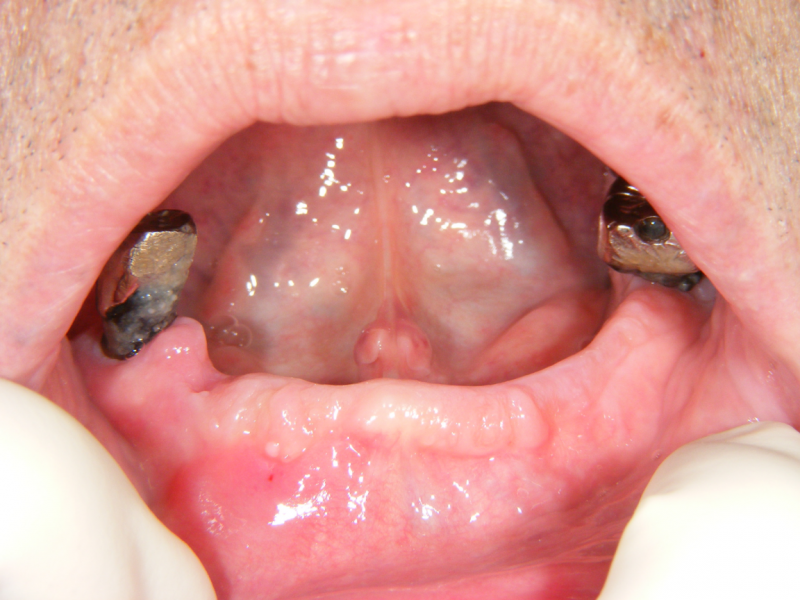

奥歯が2本残っていますが、歯周病でグラグラになっています。

義歯をお使いでしたが、残存歯の状態が悪く、義歯の調子も悪いのでインプラントを希望されました。

2本インプラントを埋入しました。直後の写真です。

このケースも、歯肉を開かずに埋入しています。